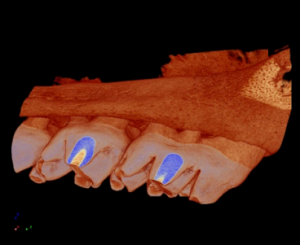

The reconstructed images can then be taken and modeled into 3D volumetric objects for quantitative analysis or visualization (Figure 3).